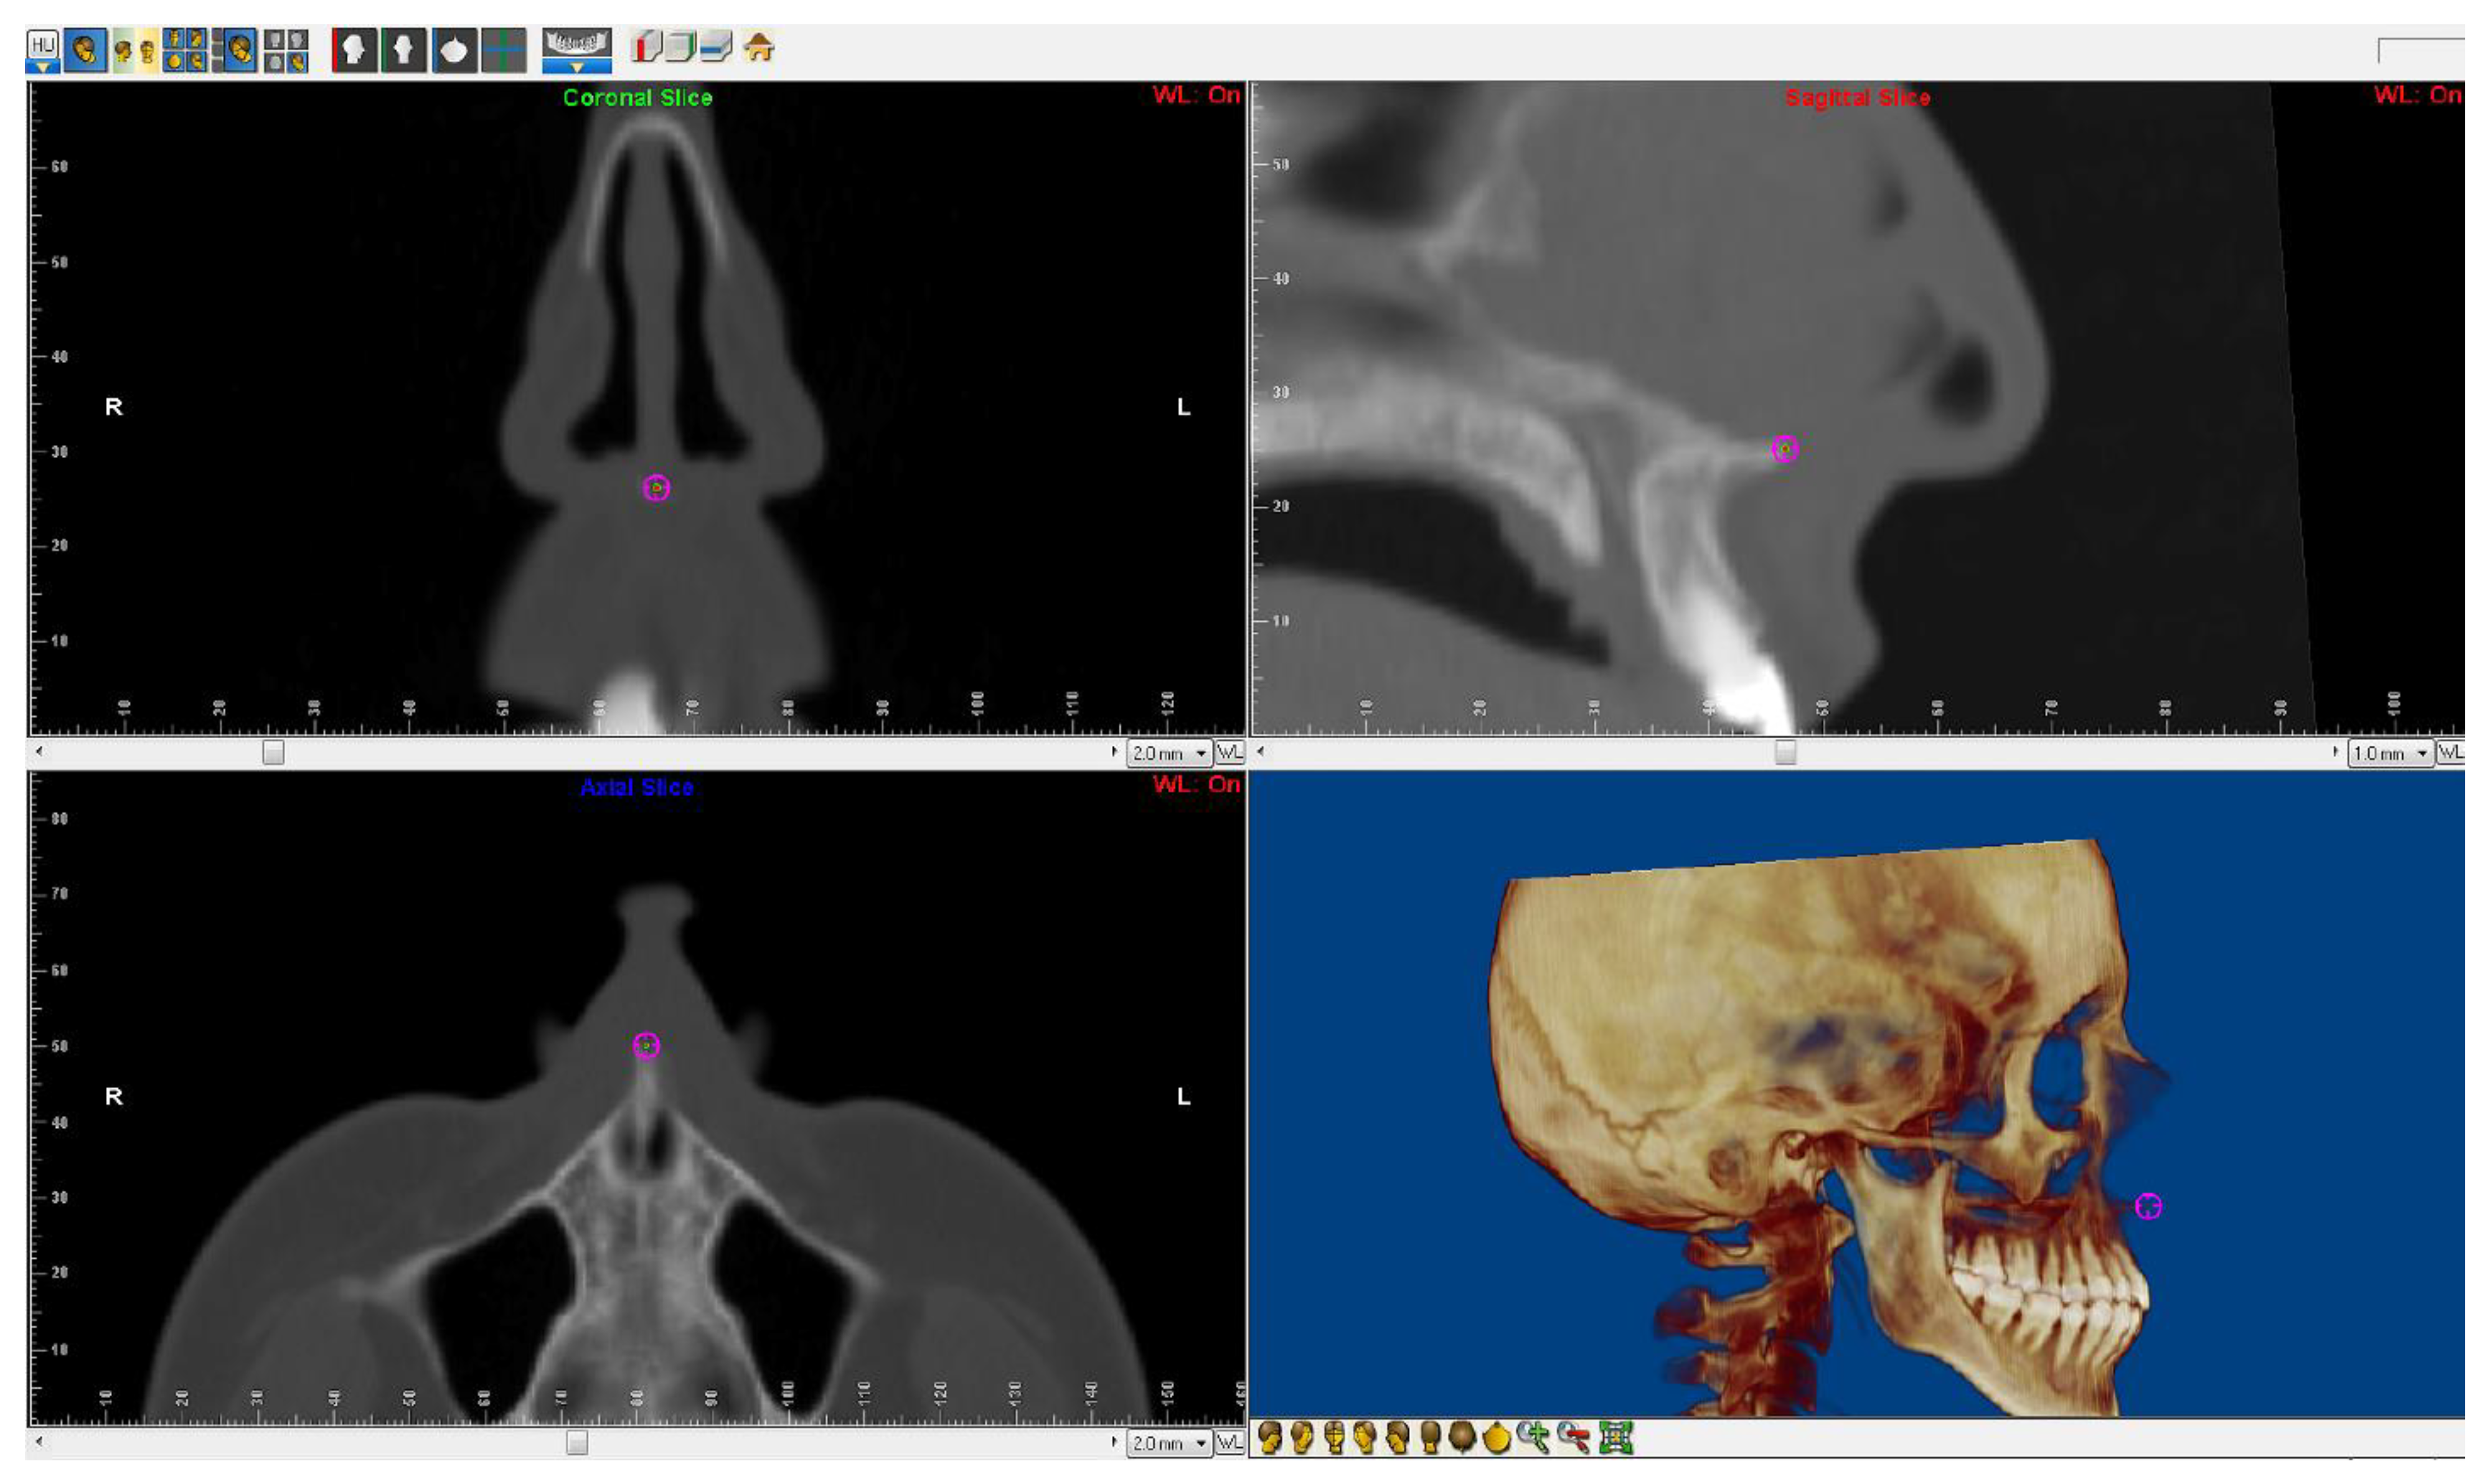

2.2. 3D Cephalometric Analysis